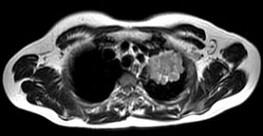

问题 男,68岁,声音嘶哑半月,行MRI检查如图,其最可能的诊断为 ( )

选项 A、左上肺癌 B、左上肺动静脉瘤 C、左上肺结核球 D、左上肺炎性假瘤 E、右上肺癌

答案 A